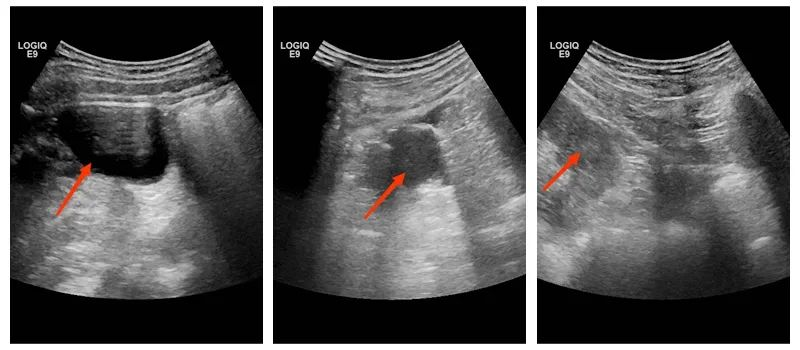

高兴副主任医师、陈钦主治医师进行右肾囊肿经皮肾穿刺抽液硬化治疗

患者,朱XX,男,在外院体检时,超声提示发现右肾多发囊肿,最大直径大于5cm,急需手术治疗。为此该患者专程来我院就诊,经超声医学科介入团队陈钦主治医师会诊,建议患者先完善检查,判断囊肿分级,我院超声医学科高兴副主任医师、陈钦主治医师带领的超声介入团队认真研判,确认患者可进行超声引导下经皮肾囊肿穿刺硬化治疗。手术过程仅用了15分钟便顺利完成,术后复查囊肿暂时已闭合,患者术后恢复良好,对我院治疗效果非常满意。

上图箭头可示术中右肾囊肿已消失